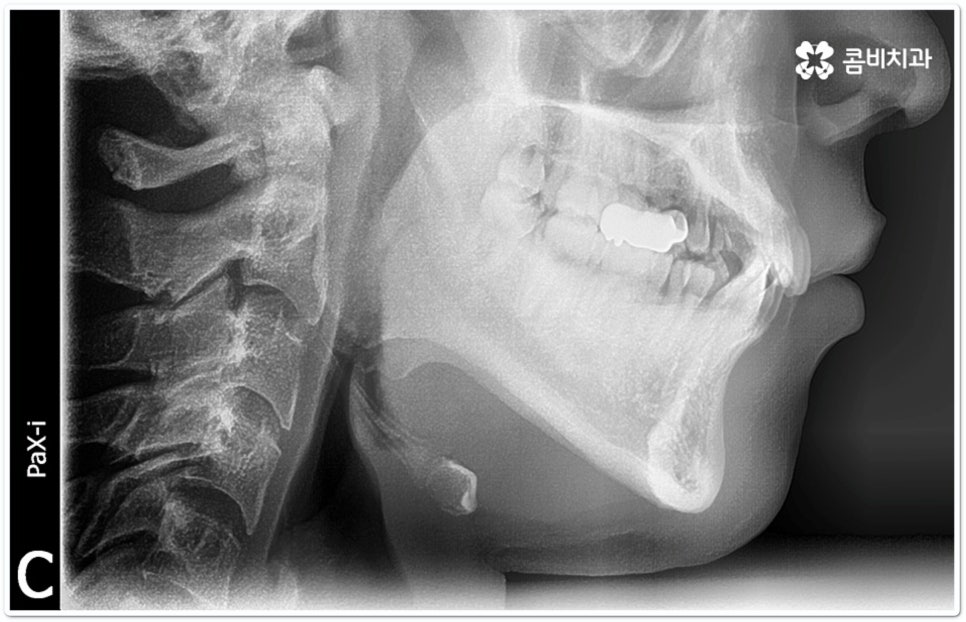

출처 아카이브 열기교정 치료는 교합이 잘 맞지 않거나 치열이 삐뚤어졌을 때 장치를 치아에 부착하여 기능성과 심미성을 회복할 수 있도록 해 주는 것으로 최근들어 관련 기술과 장치 등이 많이 발전하면서 보다 대중화되고 있습니다. 그러면서 예전에 교정을 하고 싶었다가도 오래 걸리고 불편하다, 장치가 겉으로 드러나는 것이 부담스럽다 등등 여러 가지 이유들로 인해 이를 미뤄두셨던 분들 중 다시 치과를 찾아 문의를 주시는 경우가 늘어나고 있는데요.

특히 클리피씨교정 장치는 전체 치료 기간을 단축시키고 치아 이동 통증 역시 감소시켜 주기 때문에 요즘 가장 많은 분들이 선호하고 있어요. 물론 자세한 교정 치료 과정은 환자분들마다 달라지므로 꼼꼼한 검진 및 상담을 통해 맞춤 교정 계획을 세우는 것이 무엇보다 우선시 되어야 할 것이나 장치 자체가 결과에 미치는 영향은 그다지 크지 않은 만큼 현재 가장 널리 쓰이고 있는 클리피씨교정 장치에 대해 알아보는 시간을 가지면 교정 치료를 진행하고자 하실 때 도움이 되실 거예요.

이때 부분 교정을 할 수 없다고 해서 너무 실망하시거나 부분 교정을 고집하시기 보다는 장치적인 부분에서 도움을 받을 수 있는 방법을 생각하셔서 자가결찰방식을 이용한 클리피씨교정 장치를 통해 기간적인 부담을 줄이시길 권유드리고 있습니다. 교정 관련 임상 경험이 풍부한 치과교정과 전문의 선생님과 충분한 상담을 하신다면 자신에게 꼭 맞는 교정 치료를 진행하는데 도움을 많이 받으실 수 있을 거예요.